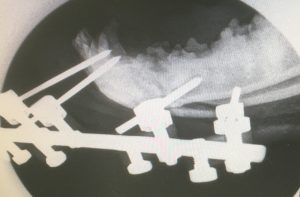

A mandibular (jaw) fracture occurred during a fracas with another dog.

Fixation employed a 4 pin external fixator. This was well tolerated and it healed well, with good occlusion (meeting of the teeth in good alignment).

Once it was united, the pins were removed under sedation a few weeks later and one of them had a lucent surround on x-ray, showing that it was loosening. This is relatively common, but it lasted long enough to do the job.